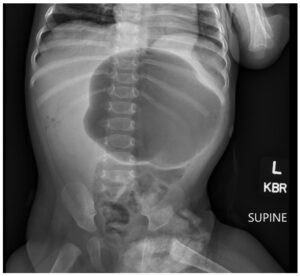

Incarcerated Gastric Volvulus and Splenic Herniation. Abdominal Radiograph. Unannotated. JETem 2025